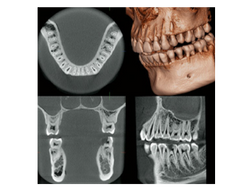

歯科用CT(歯の根の方向や、顎の骨の形を3次元で確認)

必要に応じてCT撮影(歯の根の角度や骨の厚みをより正確に確認、歯の根の動きがわかります)

歯科用CT

→ 歯の根の位置や顎の骨の状態を3次元的に把握でき、精度の高い治療計画を立てられます。